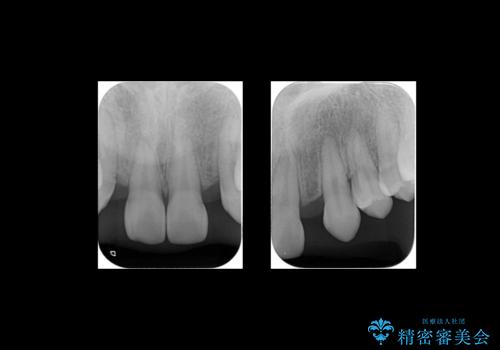

生まれつき上の歯が二本少ない状態でした。

バラバラに位置している前歯の位置を矯正治療で修正してからブリッジを装着しています。

矯正治療によって事前に歯の位置を修正しているため、ダミーの歯の大きさも調整し、自然な仕上がりにしました。また、犬歯のねじれを治してから削っているため、神経をとらずに歯の形を整えることができました。